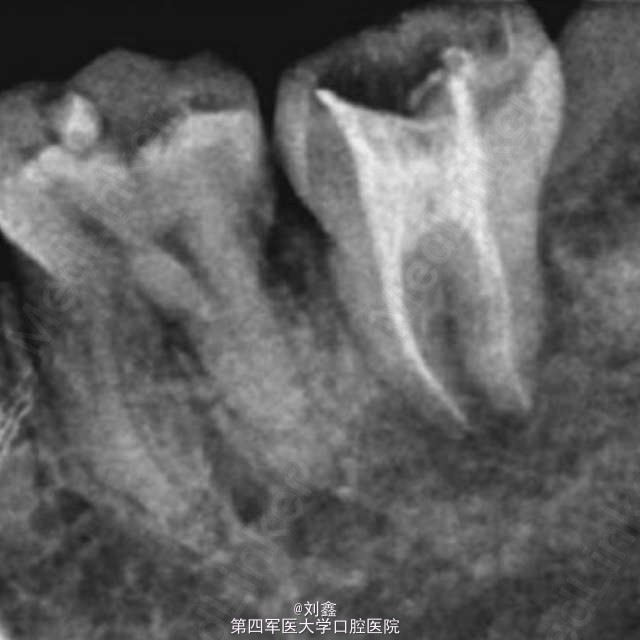

经典案例 当种植术遇上阻生牙移植

患者男,27岁,37牙残根,38牙阻生。患者不接受种植治疗,遂行阻生牙移植术。